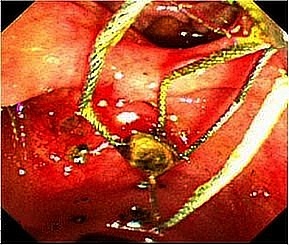

総胆管結石に対する低侵襲な内視鏡治療

胆石は胆嚢、胆管内につくられた結石のことをいい、胆管に作られた結石を総胆管結石

と呼びます。総胆管結石に対してはまず内視鏡によって胆管の出口を拡張して結石を摘

出する内視鏡的乳頭切開術(EST)を行います。胆管の出口を広げた後、結石除去用の

バスケット鉗子を胆管内に挿入して結石を除去します。ほとんどの場合は内視鏡治療で

胆管結石を除去することが可能ですが、内視鏡治療が困難と判断した場合は手術(腹腔

鏡下胆管結石切開結石除去術)で摘出します。また状況に応じて(高度な急性胆管炎を起こ

している場合)胆道ドレナージを行います。

胆管結石症に対する内視鏡治療の実際

治療手技はまず十二指腸まで挿入した内視鏡から胆管内にカテーテルを挿入し、造影剤

を注入し胆管および膵管の観察をします(内視鏡的逆行性胆管膵管造影(ERCP))。

胆管の形状や胆管内の結石を確認します。続いて総胆管結石の除去に移ります。胆管の

出口(十二指腸乳頭部)を広げるために乳頭切開を行います(内視鏡的乳頭切開術

(EST))。出口を広げた後、結石除去用のバスケット鉗子を胆管内に挿入して結石を除去

します。